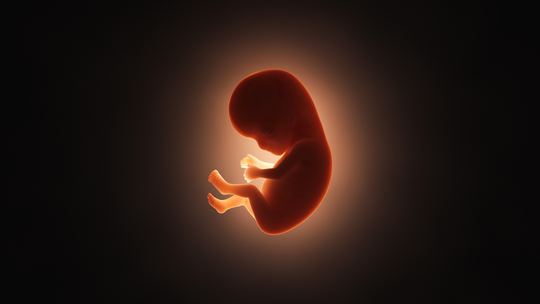

"Common Causes of Miscarriage in Early Pregnancy: What You Should Know\",\"imageid\":\"131009054\",\"imgsize\":\"1661384\",\"lu\":\"May 12, 2026, 02:25 PM\",\"id\":131009054,\"dl\":\"May 11, 2026, 03:00 PM\",\"seolocation\":\"pregnancy/causes-of-miscarriage-in-early-pregnancy\",\"subsecname\":\"Pregnancy\",\"subsecmsid\":112886004,\"syn\":\"It is very natural to experience happiness and a little anxiety simultaneously during the early weeks of pregnancy. Concerns about miscarriage are common, and many causes are not within your control. Learning about these can help you feel more supported.\",\"agency\":{\"id\":87654322},\"tn\":\"news\",\"imgratio\":\"0.5625\",\"dm\":\"t\",\"subsecseolocation\":\"pregnancy\",\"host\":\"prega\",\"slot\":\"10\"},{\"hl\":\"How Often Should You Bathe a Newborn Baby?\",\"imageid\":\"131005010\",\"imgsize\":\"35408\",\"lu\":\"May 11, 2026, 01:00 PM\",\"id\":131005010,\"dl\":\"May 11, 2026, 01:00 PM\",\"seolocation\":\"baby/bathing-newborn-baby-how-often-should-you-do-it\",\"subsecname\":\"Baby\",\"subsecmsid\":113631885,\"syn\":\"Bathing your newborn can feel both special and a little overwhelming, especially if you are unsure how often to bathe them. Fortunately, newborns do not require everyday bathing. You can take care of your baby's sensitive skin, make bathing time a peaceful experience, and create a bonding experience by knowing the proper frequency and using safe, gentle bathing techniques.\",\"agency\":{\"id\":87654322},\"tn\":\"news\",\"imgratio\":\"0.5625\",\"dm\":\"t\",\"subsecseolocation\":\"baby\",\"host\":\"prega\",\"slot\":\"11\"},{\"hl\":\"Blood Clots During Pregnancy: Understanding the Risks and Complications\",\"imageid\":\"131002969\",\"imgsize\":\"1495735\",\"lu\":\"May 11, 2026, 11:00 AM\",\"id\":131002969,\"dl\":\"May 11, 2026, 11:00 AM\",\"seolocation\":\"pregnancy/blood-clots-during-pregnancy-risks-symptoms-prevention\",\"subsecname\":\"Pregnancy\",\"subsecmsid\":112886004,\"syn\":\"Blood clots during pregnancy are a serious matter, but the positive part is that they are uncommon and usually preventable with proper awareness and care. Many expectant parents worry about this issue because pregnancy naturally changes how the blood behaves. But understanding the facts helps you stay safe and enjoy this special time.\",\"agency\":{\"id\":87654322},\"tn\":\"news\",\"imgratio\":\"0.5625\",\"dm\":\"t\",\"subsecseolocation\":\"pregnancy\",\"host\":\"prega\",\"slot\":\"12\"},{\"hl\":\"IVF Complications: What Every Couple Should Prepare For\",\"imageid\":\"130957503\",\"imgsize\":\"1771006\",\"lu\":\"May 11, 2026, 09:00 AM\",\"id\":130957503,\"dl\":\"May 11, 2026, 09:00 AM\",\"seolocation\":\"getting-pregnant/ivf-complications-symptoms-and-risks\",\"subsecname\":\"Getting Pregnant\",\"subsecmsid\":112886008,\"syn\":\"In vitro fertilisation (IVF) offers real hope to many couples facing infertility challenges. While the procedure has become much safer over the years, it still carries certain risks and possible complications. Understanding these helps you prepare better and stay alert during the journey.\",\"agency\":{\"id\":87654322},\"tn\":\"news\",\"imgratio\":\"0.5625\",\"dm\":\"t\",\"subsecseolocation\":\"getting-pregnant\",\"host\":\"prega\",\"slot\":\"13\"},{\"hl\":\"Cervical Incompetence: The Silent Cause of Second Trimester Loss\",\"imageid\":\"130956971\",\"imgsize\":\"1233562\",\"lu\":\"May 08, 2026, 07:00 PM\",\"id\":130956971,\"dl\":\"May 08, 2026, 07:00 PM\",\"seolocation\":\"pregnancy/cervical-incompetence-second-trimester-loss\",\"subsecname\":\"Pregnancy\",\"subsecmsid\":112886004,\"syn\":\"For many women, this is their first encounter with a condition called cervical incompetence, and tragically, it often announces itself only after a loss. This walks you through what it is, why it happens silently, how it's diagnosed, and what treatments and monitoring options exist to protect your next pregnancy.\",\"agency\":{\"id\":87654322},\"tn\":\"news\",\"imgratio\":\"0.5625\",\"dm\":\"t\",\"subsecseolocation\":\"pregnancy\",\"host\":\"prega\",\"slot\":\"14\"},{\"hl\":\"Can You Plan a Pregnancy After Recovering From Cancer?\",\"imageid\":\"130956443\",\"imgsize\":\"1165295\",\"lu\":\"May 08, 2026, 05:00 PM\",\"id\":130956443,\"dl\":\"May 08, 2026, 05:00 PM\",\"seolocation\":\"getting-pregnant/pregnancy-planning-after-cancer-treatment\",\"subsecname\":\"Getting Pregnant\",\"subsecmsid\":112886008,\"syn\":\"Planning pregnancy after cancer recovery is possible for many individuals with proper medical guidance. Learn about fertility considerations, safe timing, and expert recommendations to help you make informed, confident decisions about stepping into parenthood.\",\"agency\":{\"id\":87654322},\"tn\":\"news\",\"imgratio\":\"0.5625\",\"dm\":\"t\",\"subsecseolocation\":\"getting-pregnant\",\"host\":\"prega\",\"slot\":\"15\"}]}]}]]\n"])